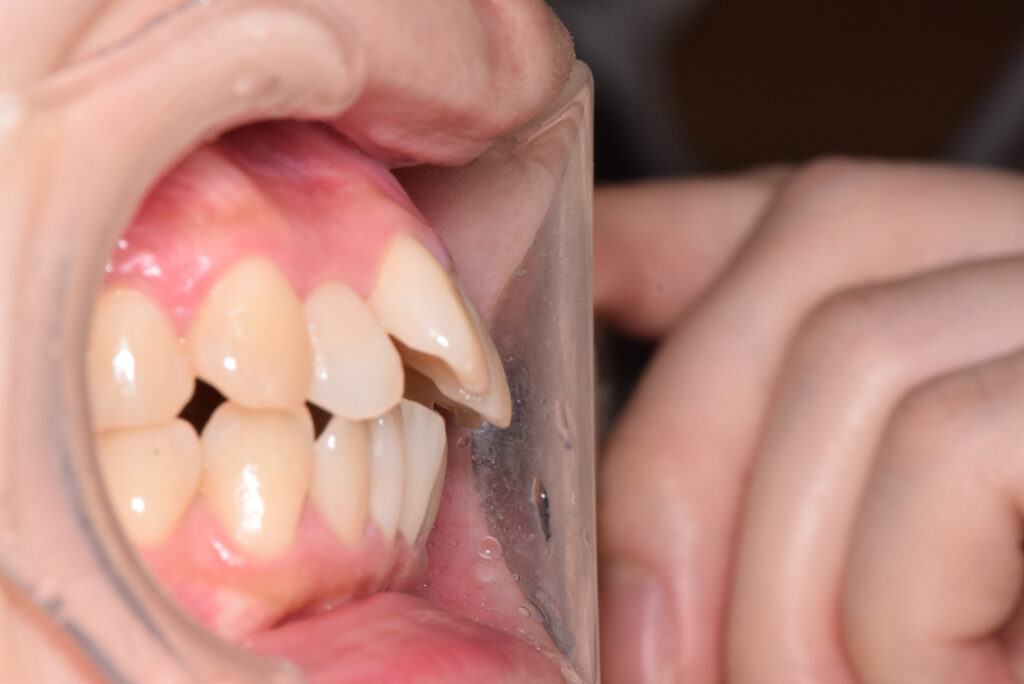

オーバージェット

治療前